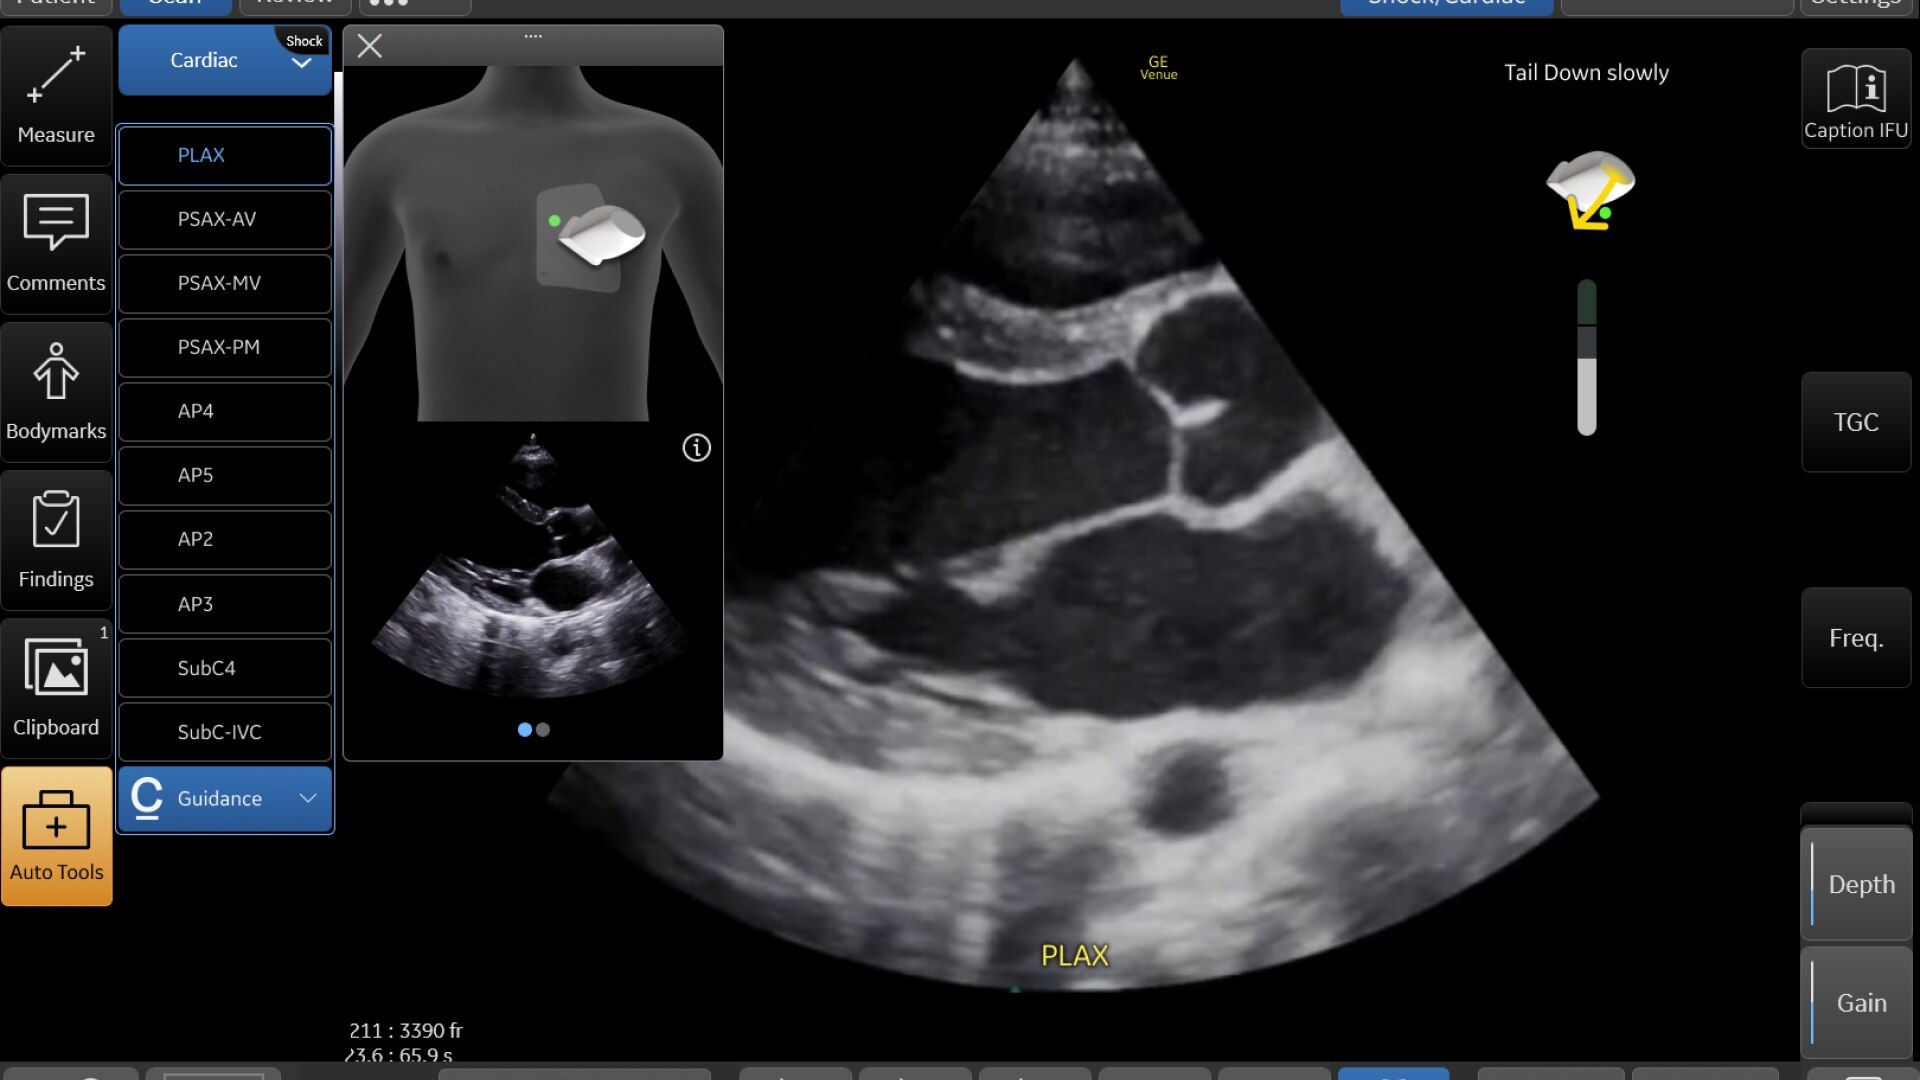

AI-DRIVEN AUTO TOOLS

Advanced and automated clinical tools enabling you to quickly diagnose, treat and determine a care pathway.

Venue Go has been designed and tested to be walk up easy for novice to expert users, and it features a number of AI-enabled automated tools to accelerate clinical workflow while also reducing the fatigue of repeated and difficult tasks. Utilizing proprietary algorithms, we synthesize data from numerous patients to ensure accurate calculations for clinical confidence.

REAL-TIME EF

For accurate, instant, and rapidly updating results

Capture precise results instantly without requiring ECGs—thanks to Real-Time EF, an AI tool that continuously calculates real-time ejection fraction during live scanning in apical 4CH view. And for improved accuracy, its integrated quality indicator helps users select an optimal view for generating exacting results. Reducing the time it takes to reach a result while helping provide consistency, a study found that Real-Time EF results are within ±10 points of experts in 86% of adult cases (80% including pediatrics).2